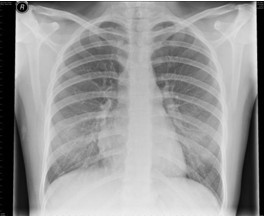

4.胸部X線檢查 哮喘發(fā)作時兩肺透亮度增加,呈過度充氣征象:并發(fā)肺部感染、肺不張、氣胸時出現(xiàn)相應X線征象。

【題】下列哪項描述符合哮喘發(fā)作時典型的X線表現(xiàn)

A.兩肺透亮度增加,呈過度充氣征象

答案:本題選A。